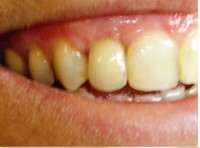

- Coroa protética cerâmica imediata

- Aplicação da cerâmica de baixa fusão direto sobre o pilar